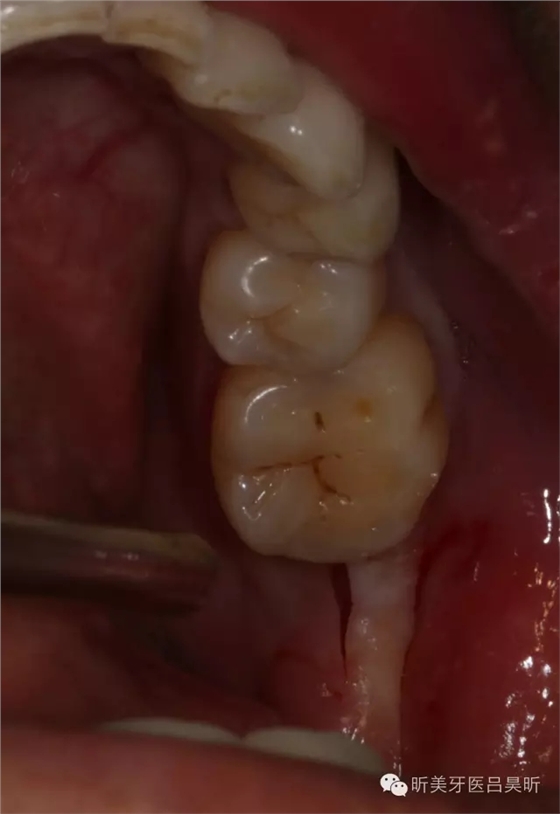

患者,男性,47缺失兩年。

術(shù)前CBCT截圖,垂直骨量似乎感覺良好

術(shù)前口內(nèi)檢查,可見牙槽骨寬度良好,角化齦量適中